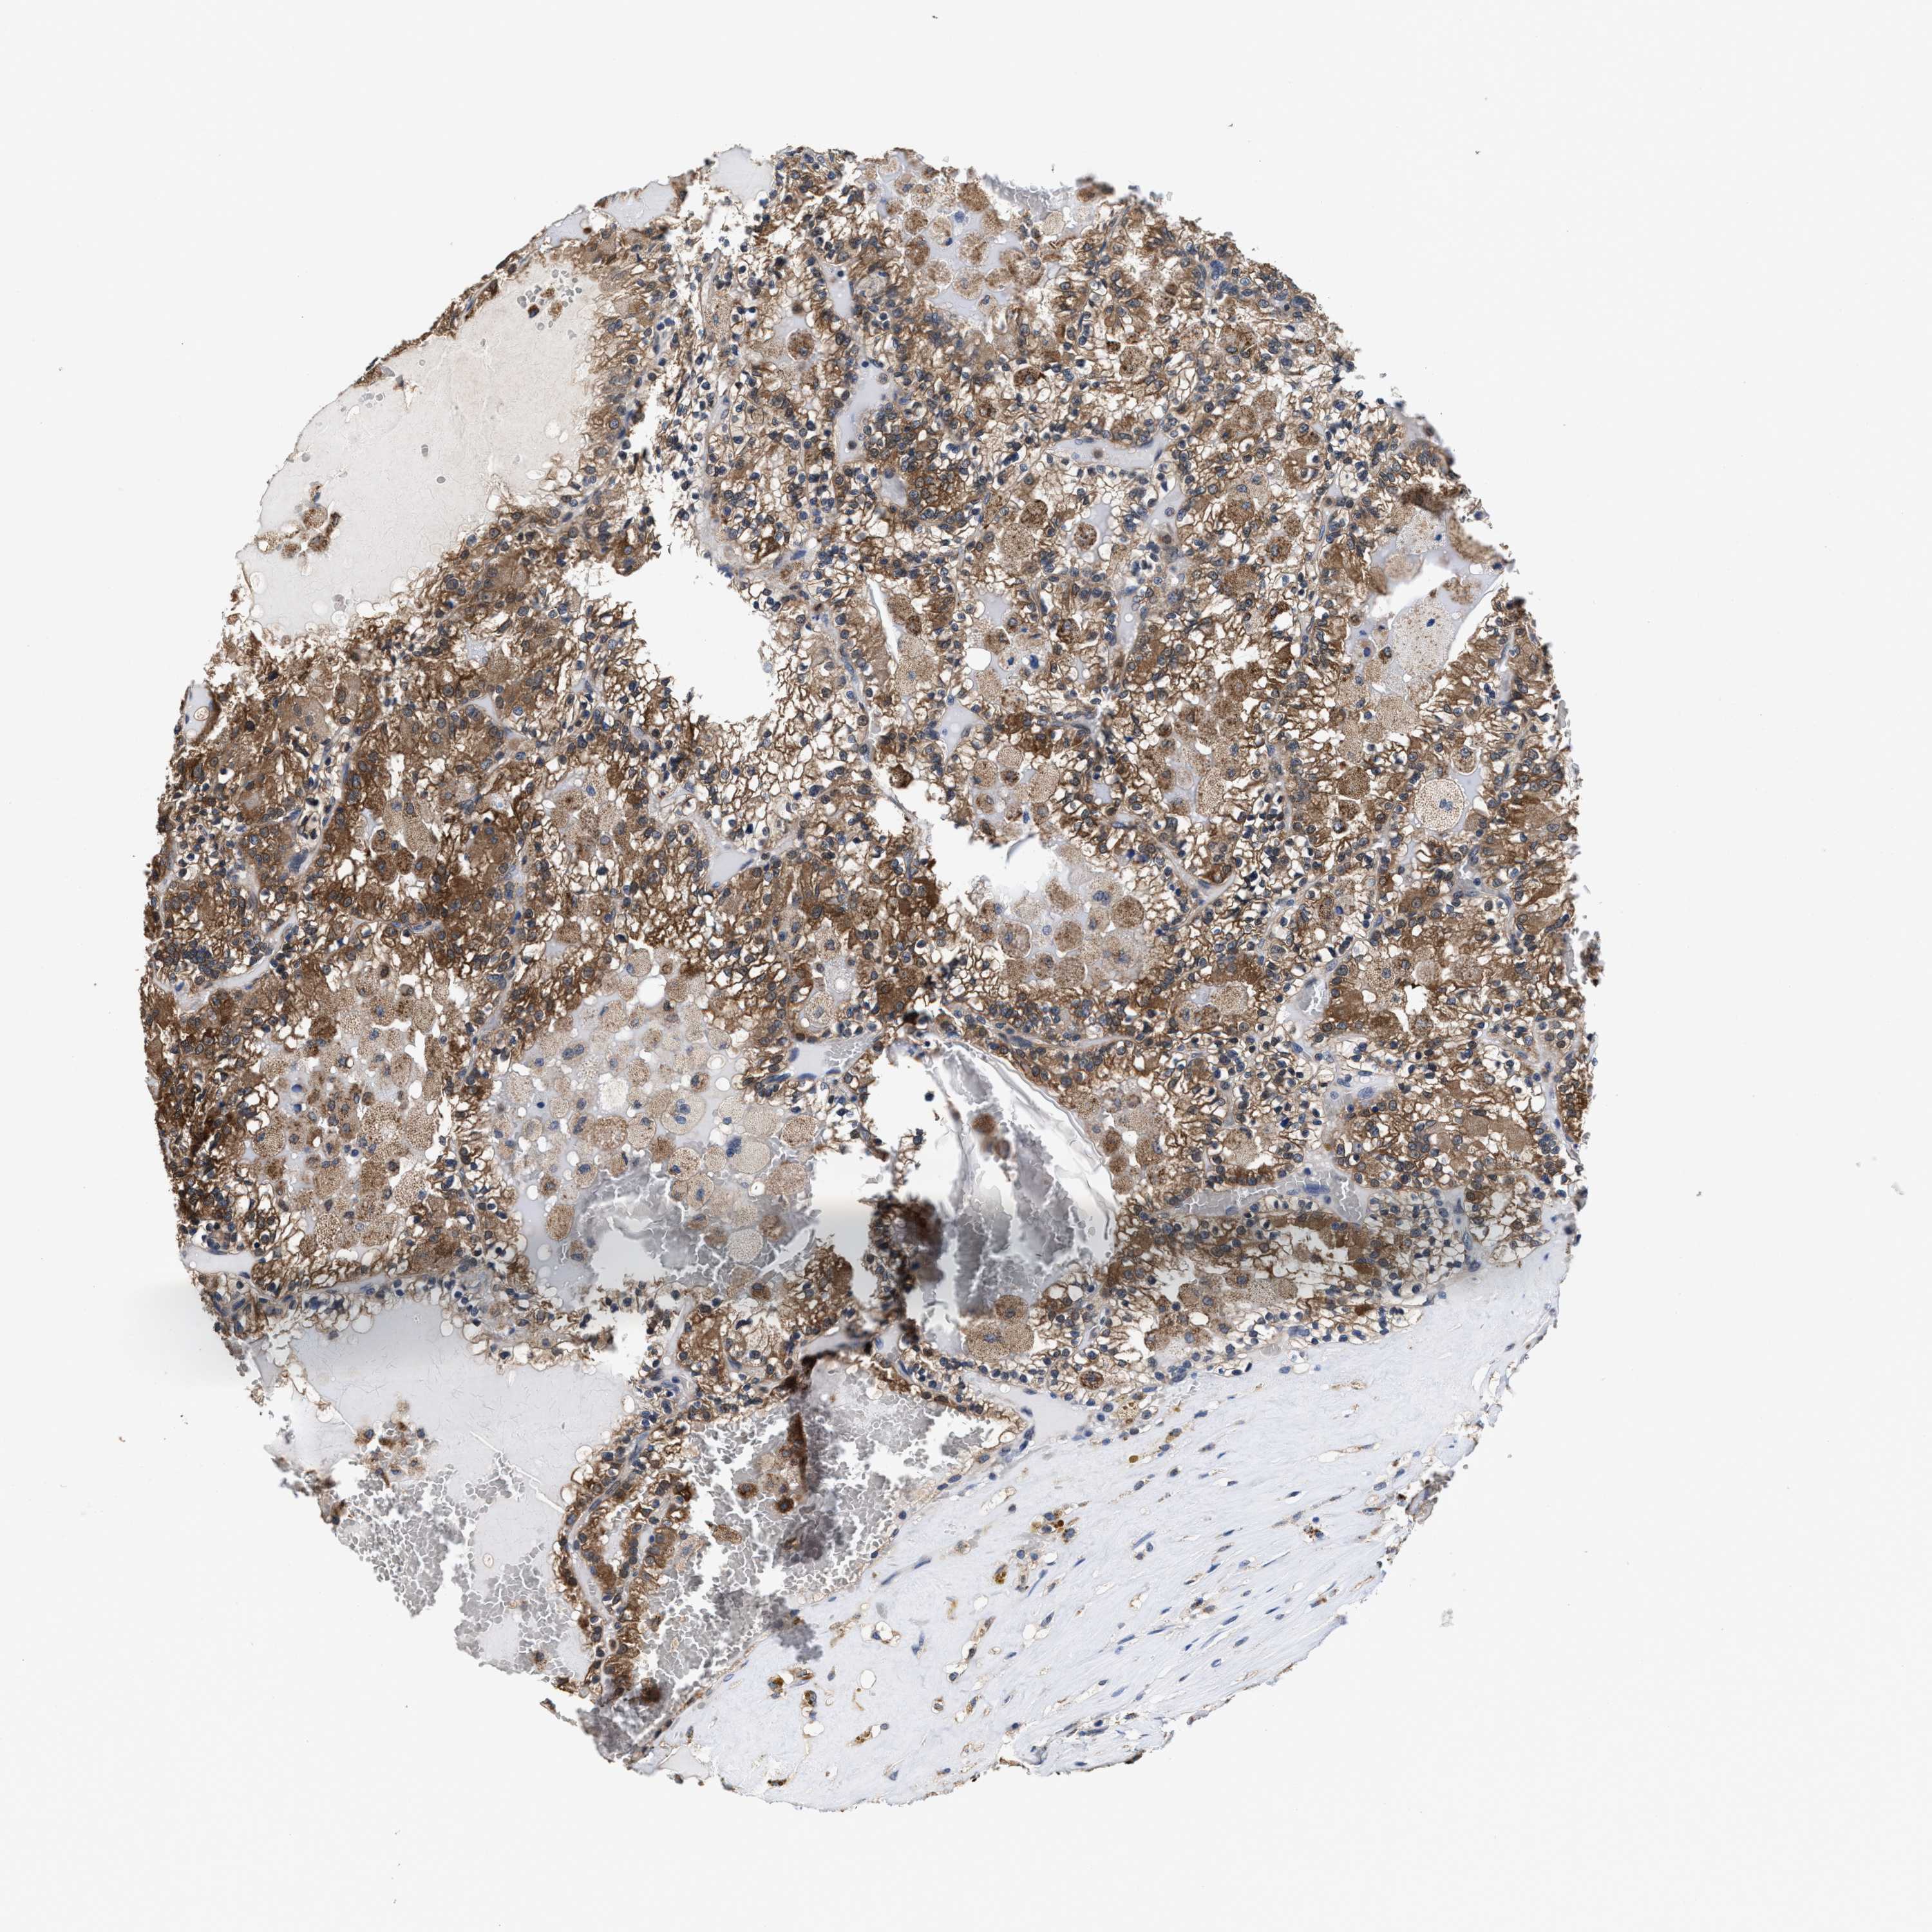

CANCER RENAL CANCER Show tissue menu

KICH TCGA KIRC TCGA KIRC VALIDATION KIRP TCGA PROTEIN RCC CPTAC PROTEIN EXPRESSION